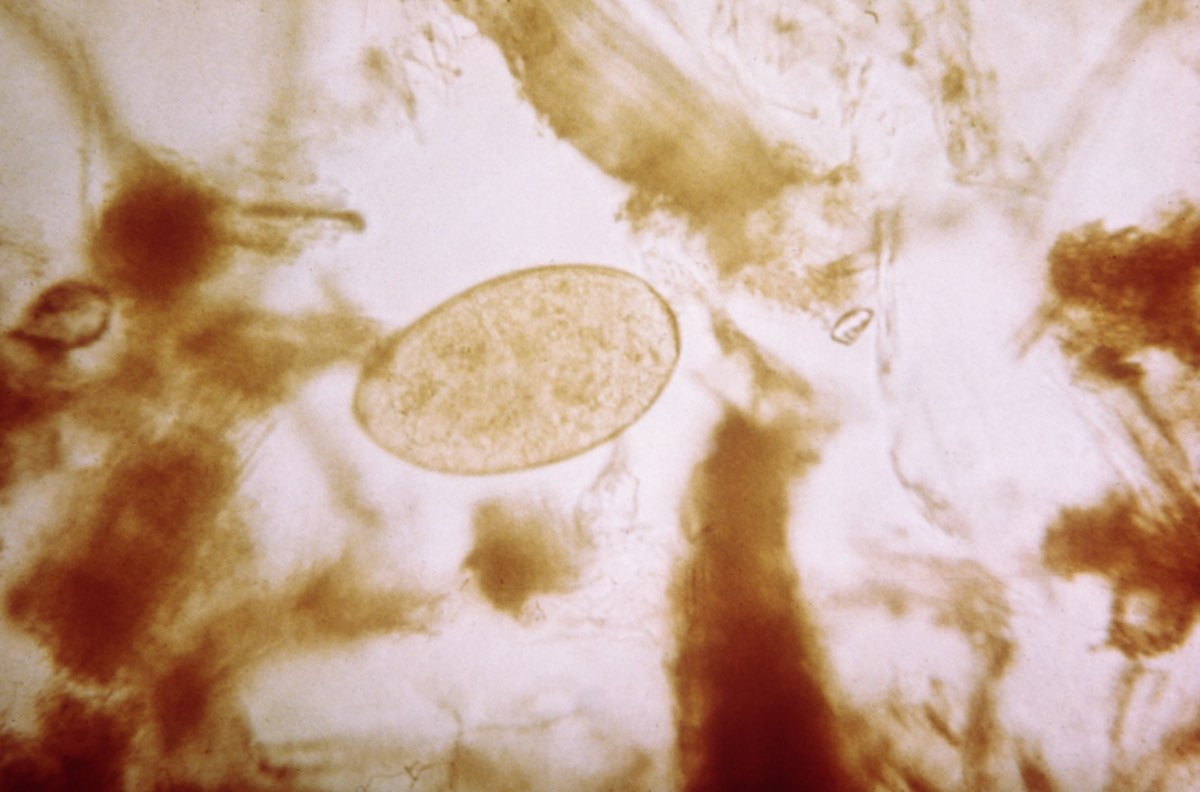

Sheep liver fluke

This unassuming ellipse is the egg ofFasciola hepatica , the sheep liver good luck . Despite its name , this trematode can infect humans , where it sets up shop in the liver and bile duct . concord to the Centers for Disease Control and Prevention , mass usually cull up an infection by consume watercress or other aquatic plants . The leech can induce chronic fervor of the liver , gall ducts , gall bladder and pancreas , according to the CDC .